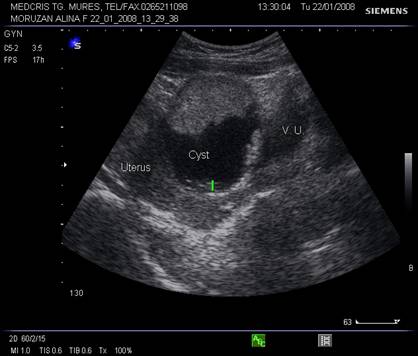

Fig. nr.387. Formatiune anecogena uniloculara cu perete subtire ( sageata ), fara lichid in Douglas ( chist functional , la o pacienta de 15 ani , la ecografia abdominala

Fig. nr.388. Chist ovarian anecogen , unilocular , cu perete subtire la ecografia transvaginala